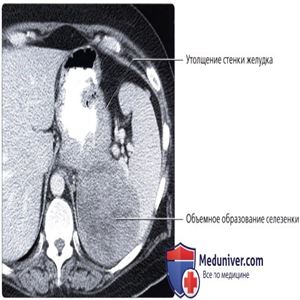

КТ с контрастированием, аксиальный срез: определяется массивное узловое утолщение стенки желудка и крупное гиподенсное объемное образование селезенки. Метастатическое поражение селезенки не характерно для рака желудка и в этом случае поставлен окончательный диагноз—неходжкинская лимфома с вовлечением желудка и селезенки.